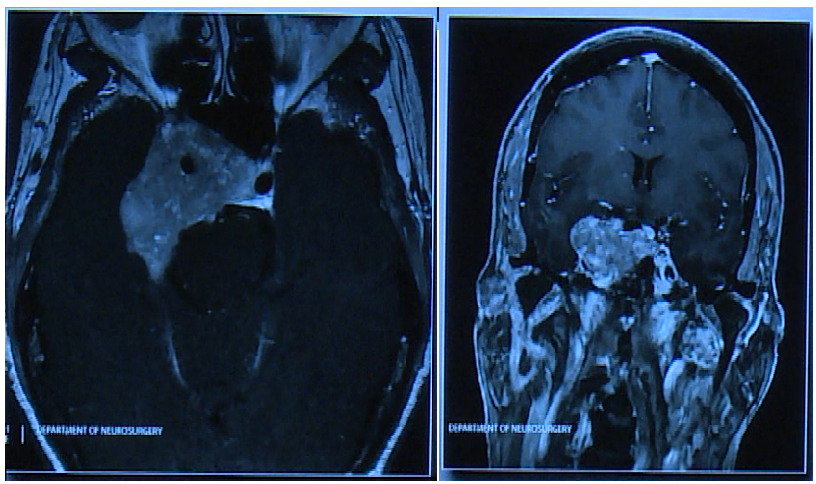

Couldwell教授演講中展示的部分較大垂體瘤

患者術前情況:62歲女性,患者35年前有垂體大腺瘤復發(fā)史,隨后接受放射治療

復發(fā)性腫瘤引起的側性眼球麻痹的進行性復視。

術后影像片子顯示腫瘤切除干凈:

術前影像顯示腫瘤較大:

由于腫瘤較大,手術策略采取了分次聯(lián)合手術入路

術后影像,腫瘤體積明顯縮小

術后影像: